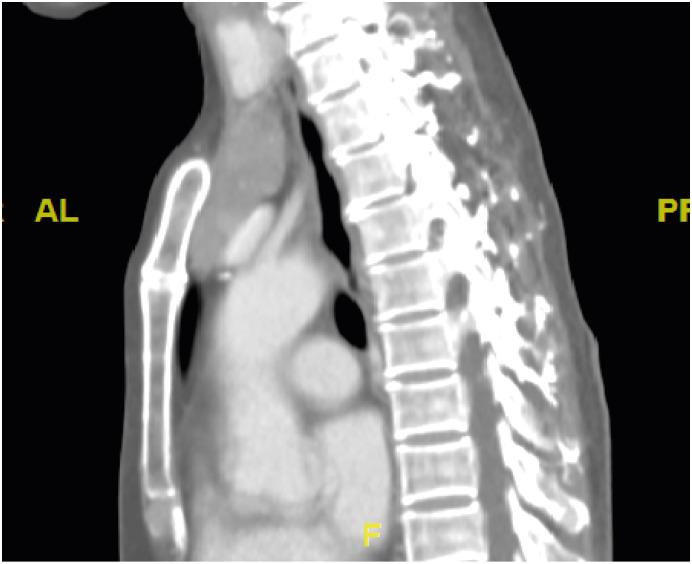

古德综合征(GS)是一种原发性免疫缺陷病(PID),多见于中老年人,伴有胸腺瘤、低丙种球蛋白血症、CD4 T淋巴细胞减少、CD4/CD8 +比值倒置以及T细胞丝裂原增殖反应受损等特征。我们报告一例62岁女性患者,最初表现为乙型肝炎病毒(HBV)再激活导致的急性肝炎,随后因反复肺炎和巨细胞病毒性肠炎反复发作而多次住院。后来发现她患有胸腺瘤和低丙种球蛋白血症,被诊断为GS。虽然T细胞在胸腺瘤免疫病理学中指导B细胞反应的重要性已广为人知,但自然杀伤细胞和CD4 +γδT细胞水平较低也可能是肿瘤发生的免疫监视低下和病毒感染清除能力减弱的原因。因此,HBV再激活后机会性感染与发现胸腺瘤的时间顺序可能反映了作为PID首发表现的免疫监视丧失。